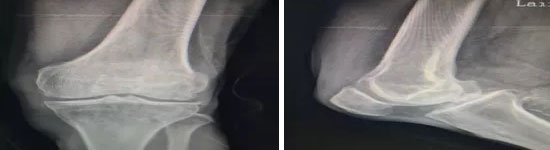

患者,向某某,男,73岁,因“左膝关节疼痛不适三年加重一年”入院,患者诉左膝关节疼痛常年影响自己的正常生活,尤其是阴雨天左膝关节更是疼痛难忍。经过州骨科专家骆渊城副院长详细检查后,决定对患者行经股内侧肌入路全膝关节置换术。

(术前资料)

(手术完成后图片)